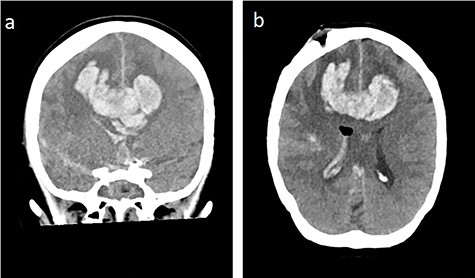

Massive progress of SAH axial cCT at the level of (a) prepontine cistern (arrow) and (b) pentagonal cistern (arrow)

During the next days, the clinical status was stable. On the 43th post-operative day, the clinical situation worsened by an epileptic state with development of maximally dilated pupils without light reaction. CT revealed a massive bifrontal bleeding with rupture into the ventricles and brain herniation (Fig. 7). On the 44th post-operative day, brain death was diagnosed.

Bifrontal intracerebral bleeding with brain swelling and herniation: (a) coronal cCT, (b) axial cCT